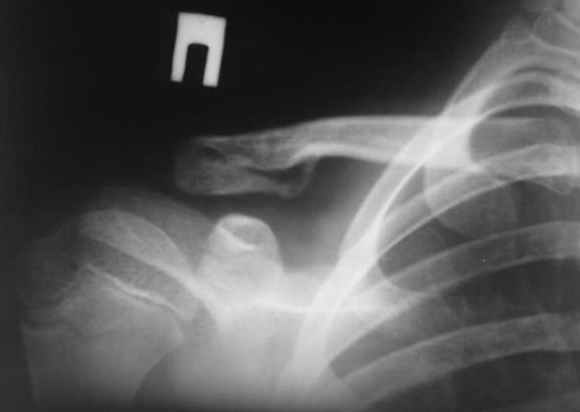

Представлен исход консервативного лечения молодого человека с закрытым переломом акромиального конца правой ключицы после 1,5 мес.

Результат, на мой взгляд, говорит сам за себя. Объем движений в суставах правой верхней конечности полный. Боли отсутствуют. Патологической подвижности в области перелома нет. Еще месяц и перелом срастется окончательно. Спасибо всем за "виртуальный консилиум".

Прямая проекция даёт лучшее представление о взаиморасположении фрагментов, на представленном снимке направление Х лучей - снизу-вверх.

В приведённом случае -это не критично, перелом срастается, при АС сочленении повреждениях прошу радиографов придерживаться стандартов методики.